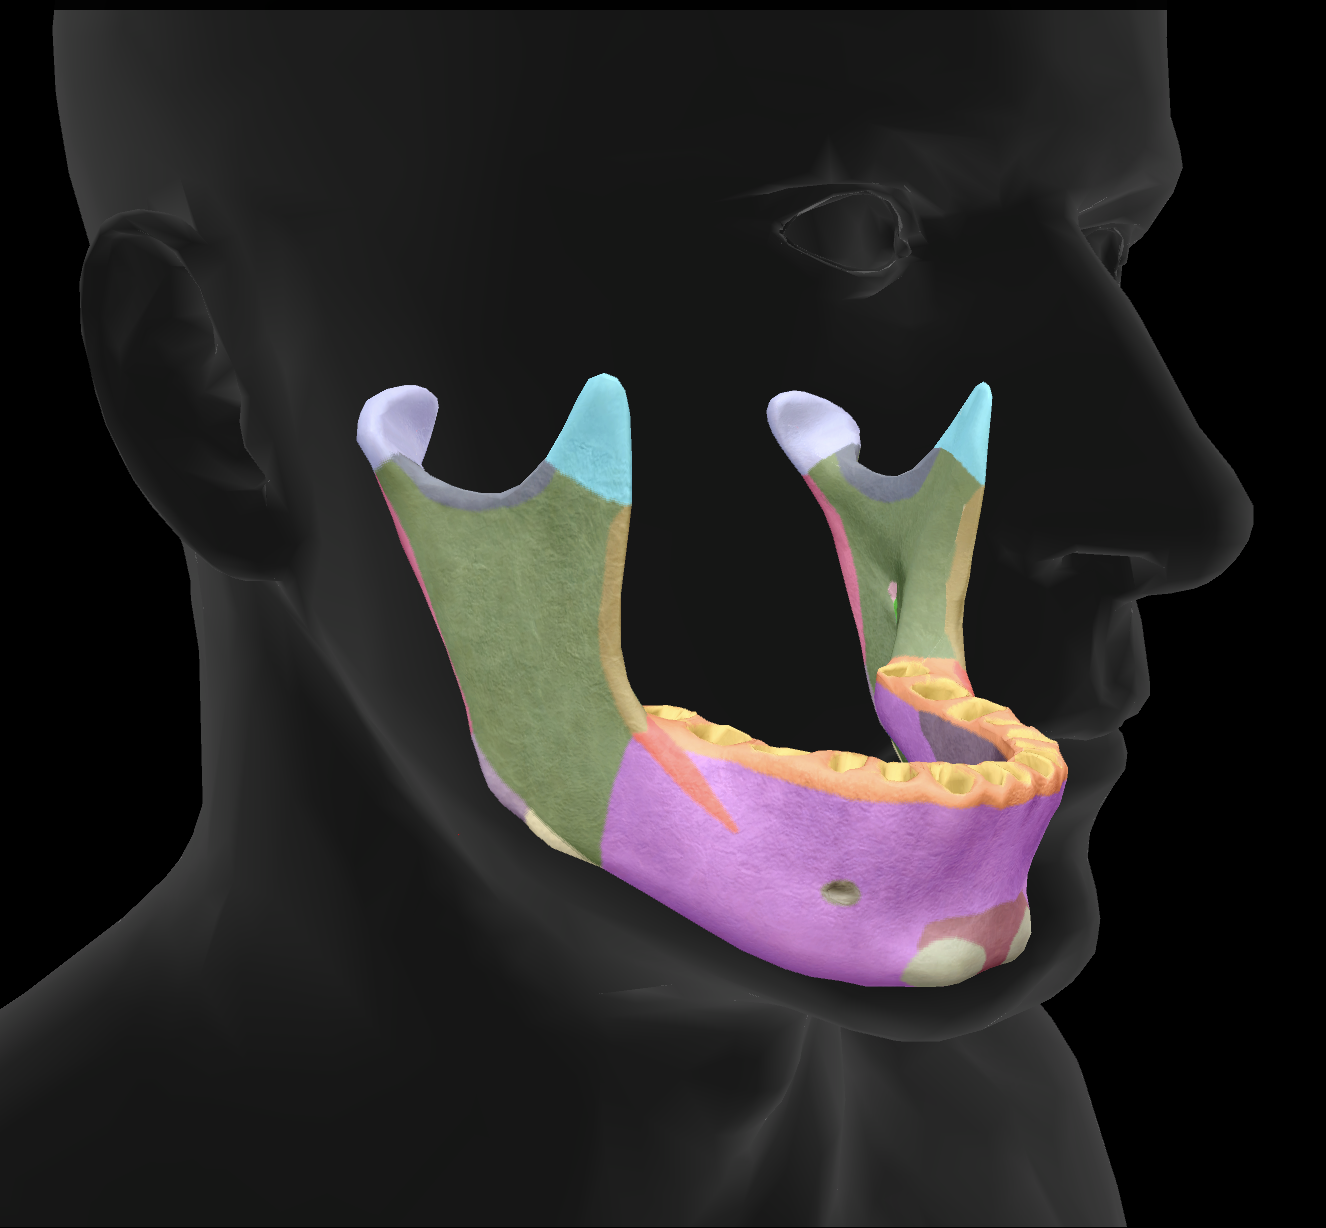

What bone is this?

mandible

What is the name of this feature?

mental foramen

What is the name of this feature?

mandibular condyles

What is the name of this feature?

ramus

What is the name of this feature?

alveolar process

What is the name of this feature?

mandibular notch

What is the name of this feature?

angle

What is the name of this feature?

body

What is the name of this feature?

coronoid process

What is the name of this feature?

mental protuberance